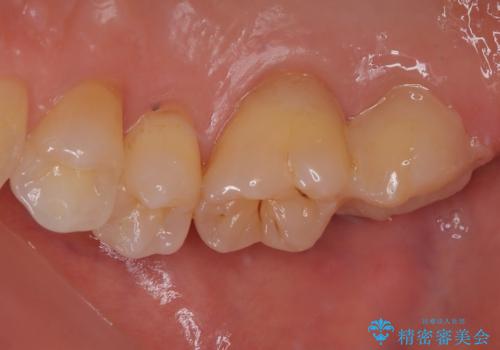

根管治療を行った奥歯は、再発防止や残された歯質を守るため、クラウンによる補綴治療が必要となります。

補綴後6ヶ月経過しレントゲンを撮影したところ、根尖周辺の病変が消失していることが確認できました。